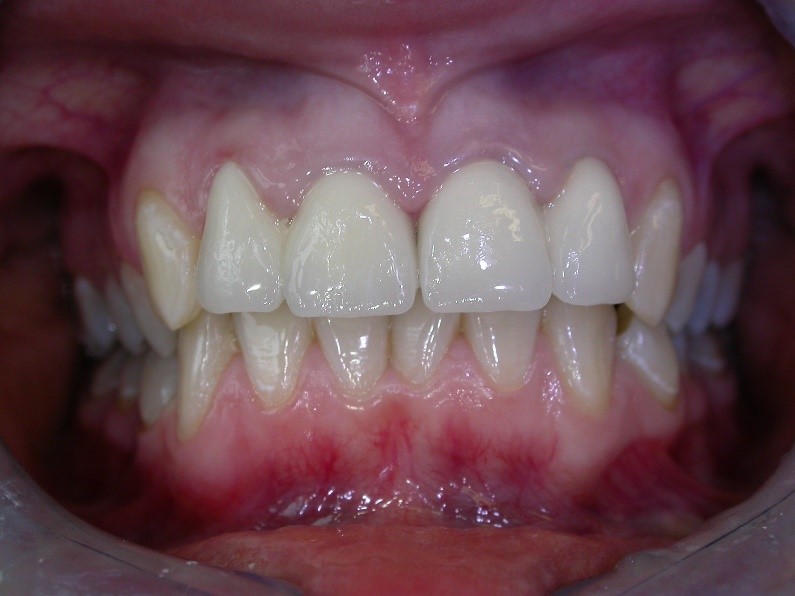

Úprava estetiky chrupu pomocí laboratorně zhotovených keramických korunek.

Korunky zhotovujeme u velkého poškození zubu nebo z estetických důvodů. Nejčastěji používáme celokeramické korunky a metalokeramické korunky. Ošetření probíhá ve dvou návštěvách, v první návštěvě je nutné zub nabrousit a udělat otisk, který posíláme do laboratoře. Z ordinace odcházíte s dočasnou korunkou, která brání pohybu sousedních zubů a mechanicky chrání připravený zub. Po 10ti dnech, tedy času, který potřebuje laboratoř, Vám po sejmutí provizoria, odevzdáme Vaše nové korunky.

Ukázky naší práce